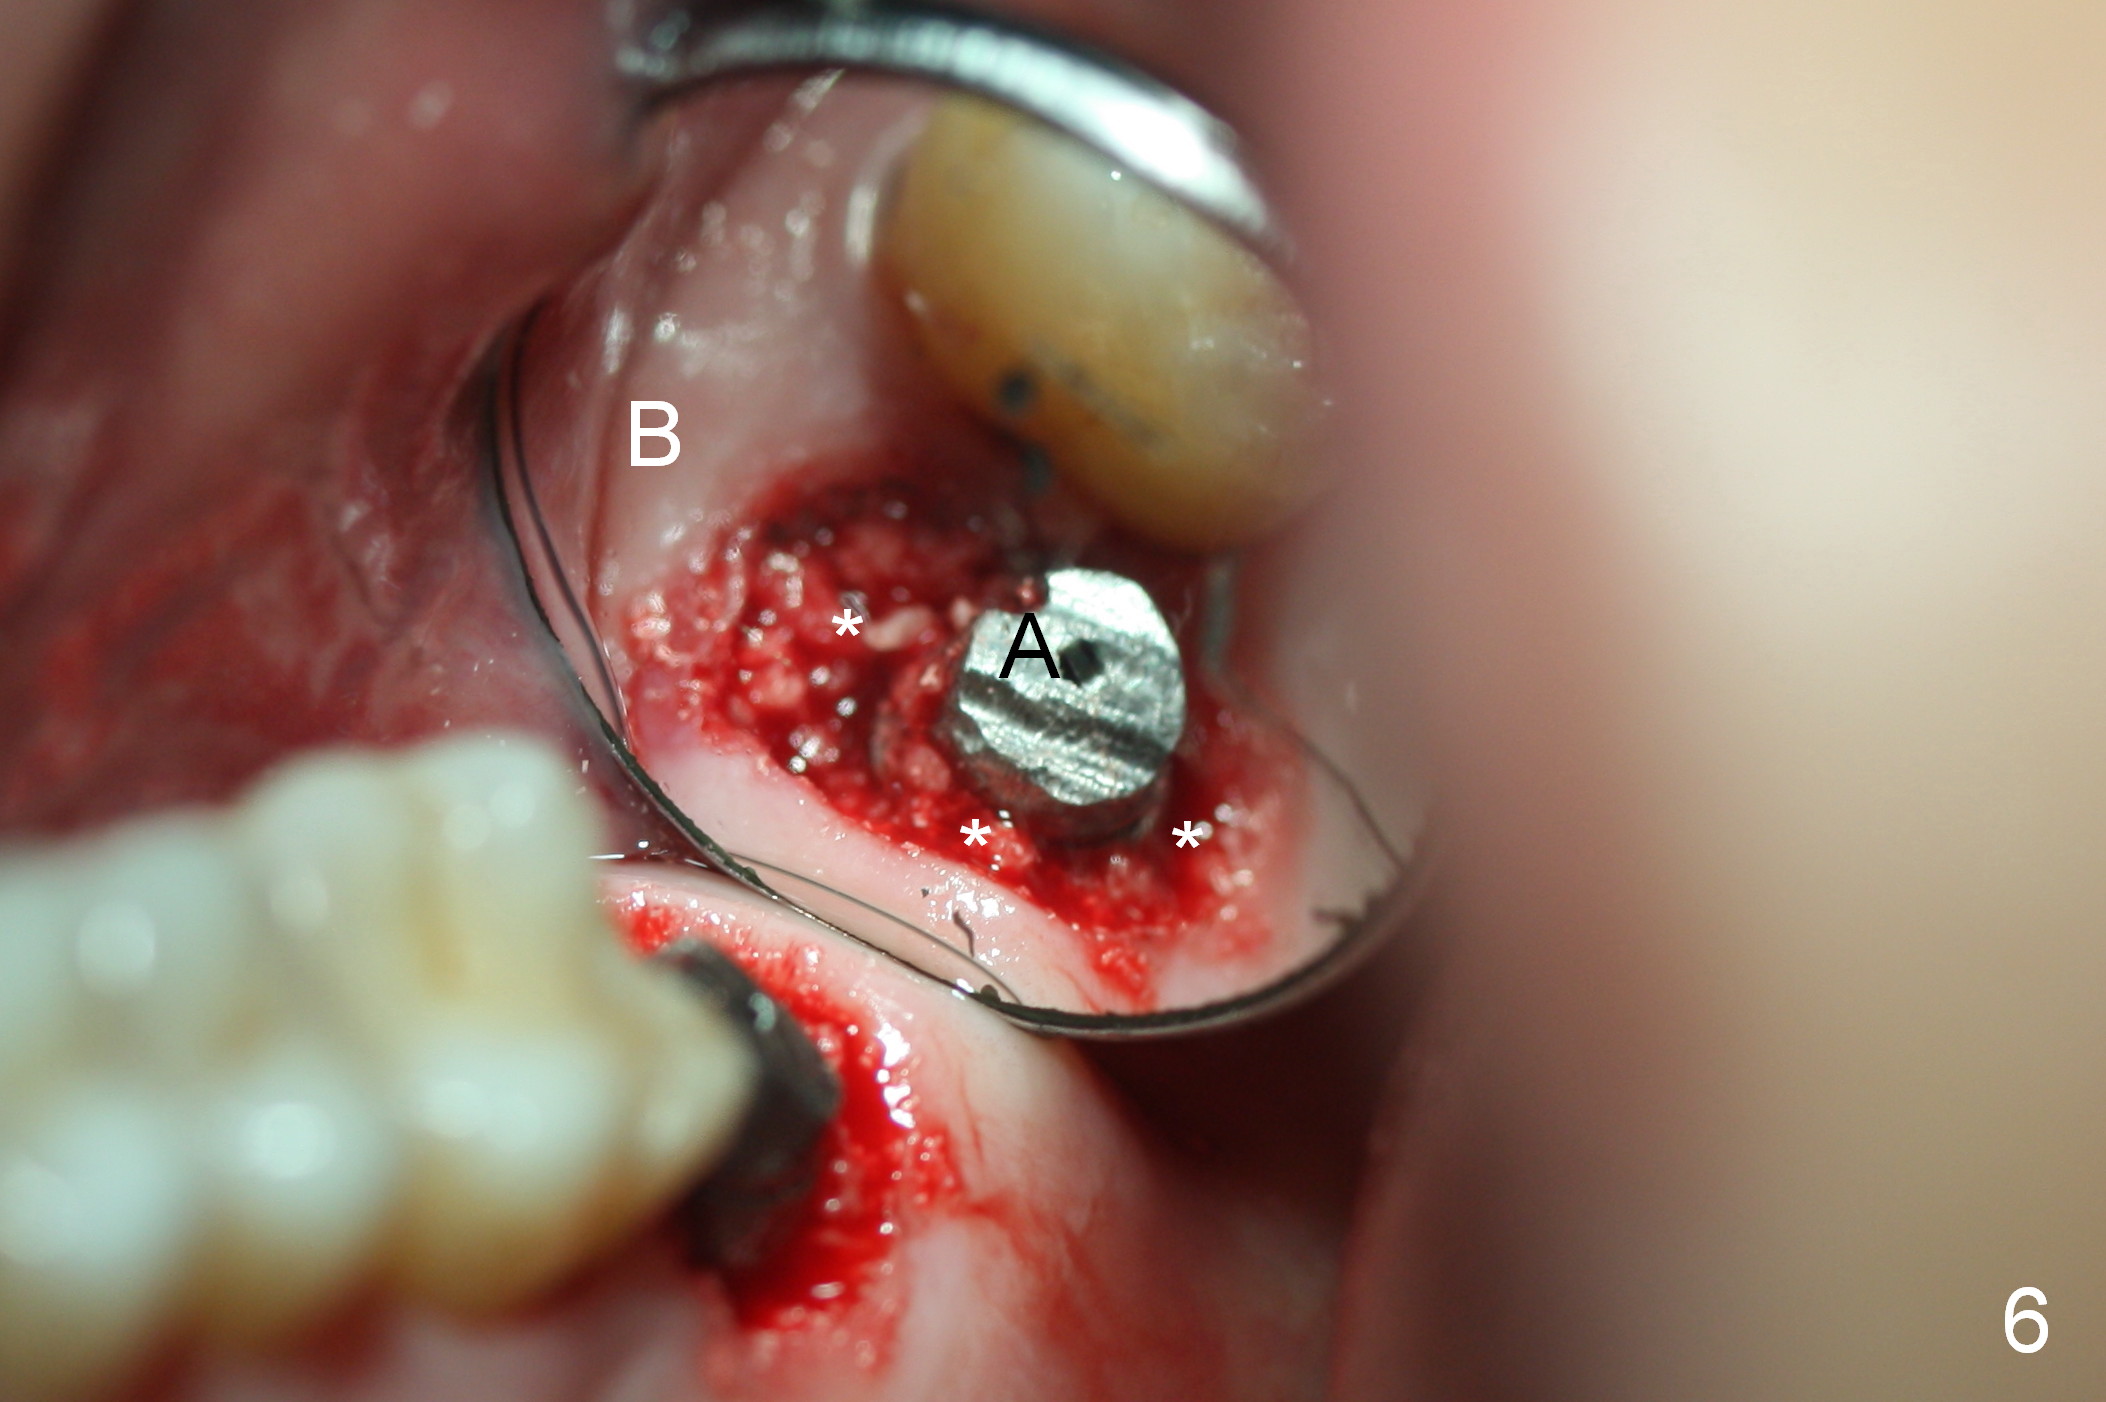

A 50-year-old man (TK) had sign & symptom of crack tooth at #15 (Fig.1) and chose to have root canal therapy done by a specialist. One month later, he returns for crown; exam reveals a crack line mesiodistally (Fig.2). The patient agrees to have immediate implant (Fig.3 design: 6x14 mm). The buccal roots fracture upon luxation. Osteotomy starts in the septum with a 2 mm pilot drill and deviates to the palatal socket, followed by 2, 3, 4 mm tapered osteotomes. A series of taps are placed: 6x17 mm one achieves stability (Fig.4). When the latter is removed, there is no sign of sinus air leakage. A 6x14 mm implant (Fig.5 I) and a 5x3 mm abutment (A) are placed. After abutment height adjustment, an immediate provisional is fabricated. Allograft with Osteogen is placed in the remaining sockets and gaps (Fig.6 *). Fig.7 shows the inner side of the provisional with double arrows indicating the dimension of the abutment, whereas arrowheads the dimension of the socket buccopalatally. When the provisional is cemented (Fig.8 P), it completely seals the socket. As long as the provisional stays, bone graft will not be lost.